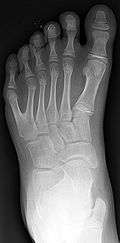

Classification is performed by using x-ray imaging to see the bone structures.[15]

The Wassel classification is the most widely used classification of radial polydactyly,[8] based upon the most proximal level of skeletal duplication. The most common type is Wassel 4 (about 50% of such duplications) followed by Wassel 2 (20%) and Wassel 6 (12%).[8]